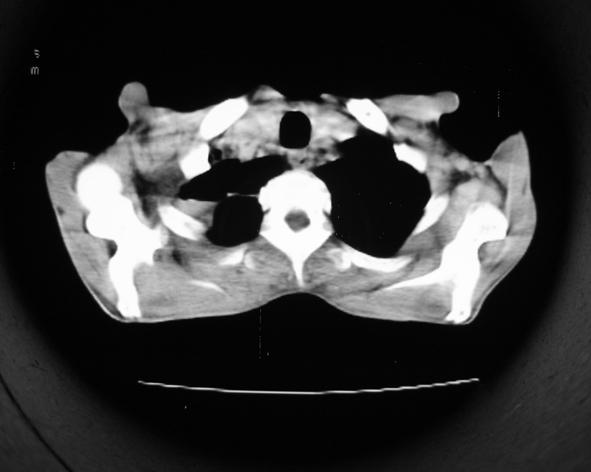

男53岁,咳嗽气短,以往身体健康.

右肺上叶多发多形态空洞及增殖灶,可见团块钙化,胸膜肥厚、粘连,考虑继发型肺结核可能性大

1.右肺上叶干酪性肺炎,2。肺气肿,肺大泡